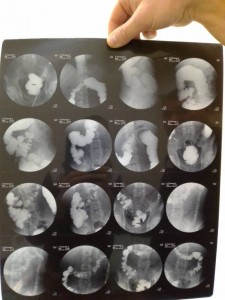

Срочно нужна помощь на приобретения лекарства 2000 тр , денег нет ,недавно лежал в хирургии 1 гороцкой больнице прогноз не утишительный , выписался до нового года а проблема осталось поставили диагноз : воспаления кишечьника, спайки, и язвы желудка если кто не равнодушен помогите , Киви кошелек +79012830491 за ранее спасибо просто боли не выносимо

Деньги на лекарства - IMG_20191209_163357.jpg

Деньги на лекарства - IMG_20191209_163328.jpg